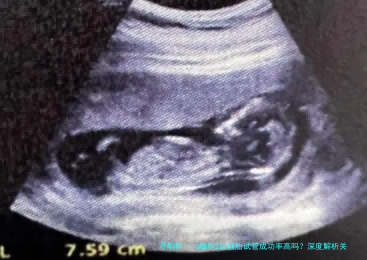

6细胞2级胚胎试管成功率高吗?深度解析关键因素与临床数据

在试管婴儿治疗中,胚胎质量是决计成功率的核心因素。6细胞二级胚胎作为临床多见的中级质量胚胎,实际上际妊娠潜力备受留意。本文将从国际胚胎评介体系体例切入,结合最新临床数据,系统剖析该等级胚胎的着床规则及影响要点。